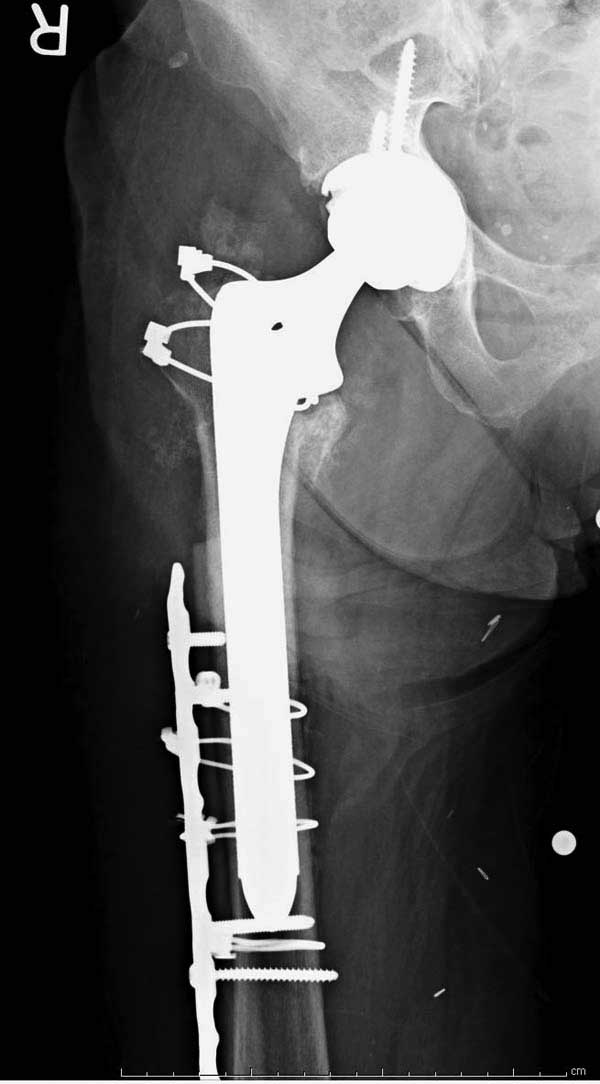

Третья операция-продолжения усилии "синьорами пэрами" по разрушению нормальной анатомии. Крест на головку! По видимому возраст позволяет биполярную конструкции, и при дефекте  calcar пошли на обычный цементный. Ягодичные мышцы потеряли связь с вертелом, т.е. отсутствует верхний удержатель, и результат “a Big Screw Up!” Снимки вызывают головокружение!

Если хирурги не устали от своих “творчеств”, тогда можно ре-оперировать с calcar replacement stem, и собрать остаток ягодичных мышц. Глубина и отстутствие артроза позволяет применить любой, биполярный или тотальный, хотя принять решение можно после ревизии ацетабулума.